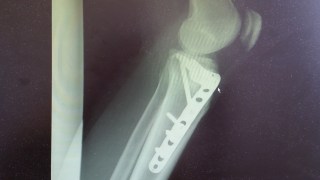

脛骨高原骨折

骨折日記41:高原骨折から848日 抜釘手術から479日経過

2017年5月7日 カブカップでの脛骨高原骨折から848日(2年3か月26日)が経過し、その後足に埋めた骨を結合するためのチタンプレートを外す抜釘手術から479日(1年3か月22日)が経過しました。最近の様子をご報告。今年の7月から勤務地が...